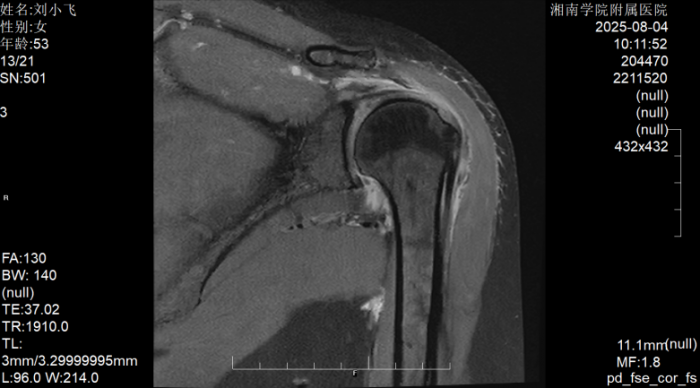

据了解,患者刘阿姨因左肩部疼痛辗转求医多日,尝试吃药、针灸、推拿等多种治疗后症状不仅未改善,反而持续加重,最终发展到无法端碗吃饭、自行穿衣洗澡的程度。转诊至湘南学院附属医院后,经术前MRI检查确诊为巨大肩袖撕裂,且肩袖缺损范围大、肌腱质量差,传统修复方式难以达到理想效果。